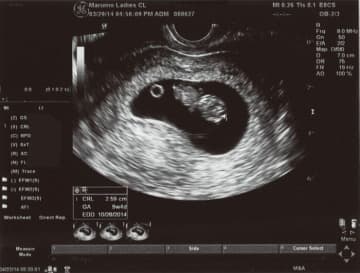

【医師監修】産科医がビジュアルで解説します!「超音波写真(エコー写真)の見方」ガイド

妊娠して初めて経験する超音波(エコー)検査。おなかの赤ちゃんと会える楽しみな時間ですね。でも、超音波...